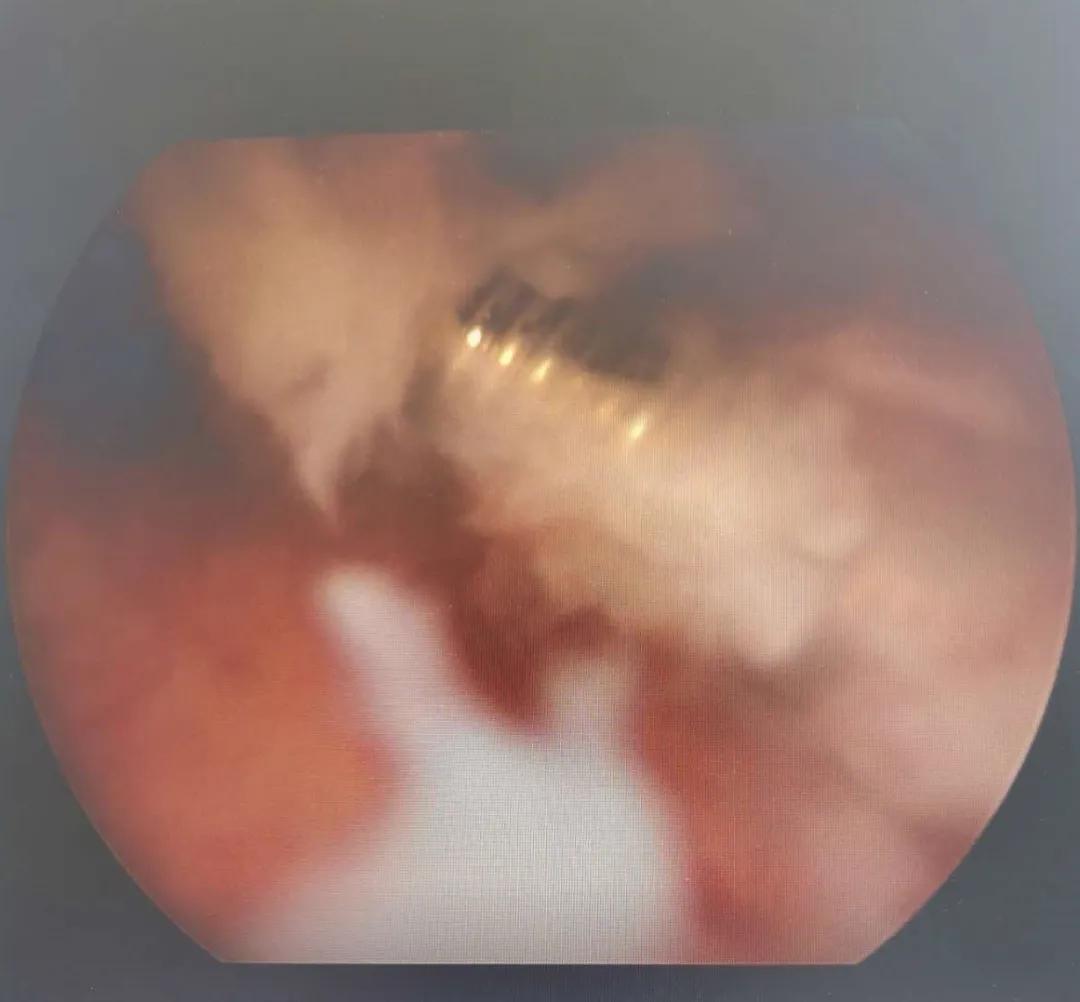

术前经过精细检查,结合超声和定位X线平片,我们判断残留节育器约3厘米,嵌顿于子宫肌层内,科室讨论后决定手术方式为经宫腔镜节育器取出备腹腔镜监视。由安医二附院专家范懿隽主任及王青元医生亲自主持宫腔镜检查+镜下残余节育器取出术。宫腔镜下见近宫腔中段处可见一实性隔样组织将宫腔分为上下两部分,宫腔内外全不可见外露的金属,这种情况下常规盲操作是无法探及节育器的。置入宫腔镜专用剪刀,直径仅0.5毫米,剪开覆盖于金属环表面的内膜组织,见断裂金属环,两端深深插入两侧壁肌壁间,同时导致宫腔内形成纤维束状粘连。微型剪刀分离两侧壁纤维束状粘及环表面黏膜完全暴露残余环。取环顺利,用时短,术中出血极少,患者及家属非常满意!